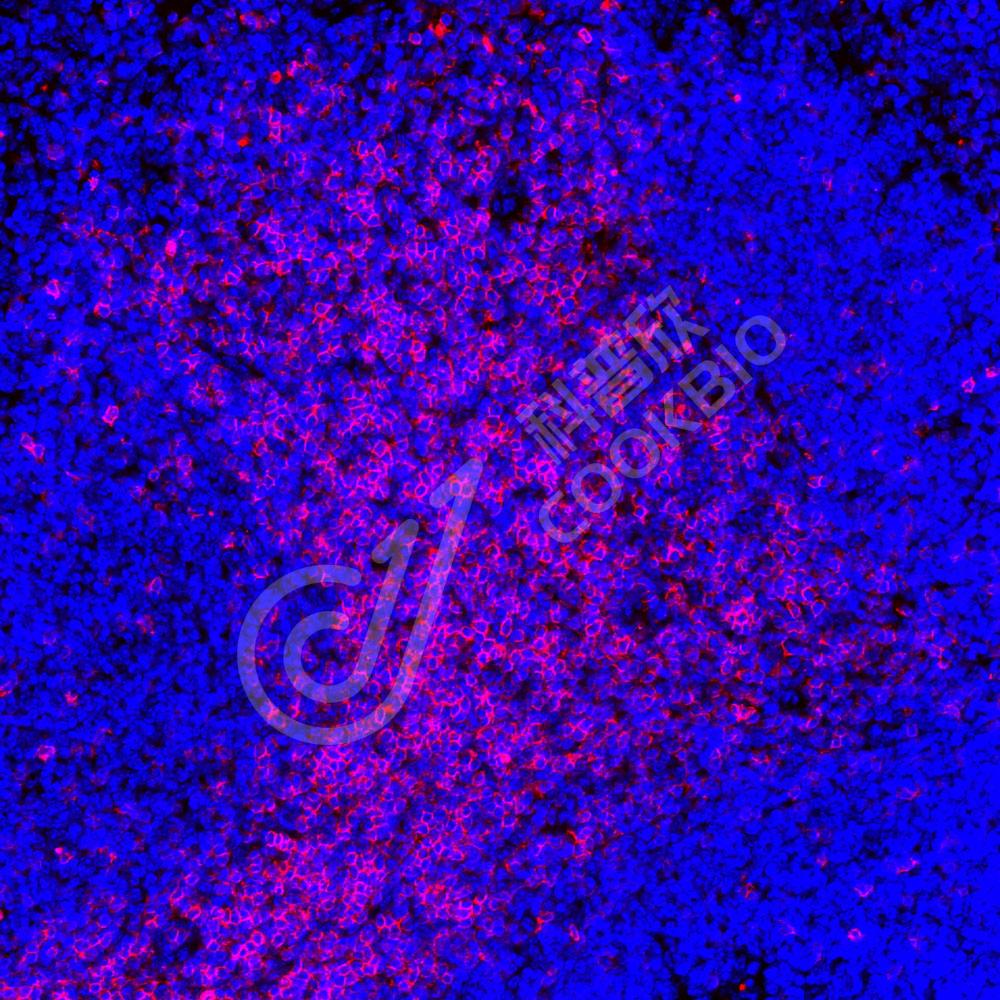

IF检测CD3蛋白(货号 K236042)(红色).

样品: 小鼠脾, 4%多聚甲醛 (货号KSG1101) 固定12-24小时.

抗原修复: 柠檬酸抗原修复液(干粉, pH 6.0) (KSG1201), 高压锅均匀喷气计时2分钟.

封闭: 3% BSA(货号KSGC305010)的PBS溶液, 室温孵育30分钟.

—抗: 1: 1000稀释, 4℃ 孵育过夜.

二抗: Cy3标记山羊抗小鼠IgG (H+L) (货号KB63903), 1: 300稀释, 室温孵育1小时.